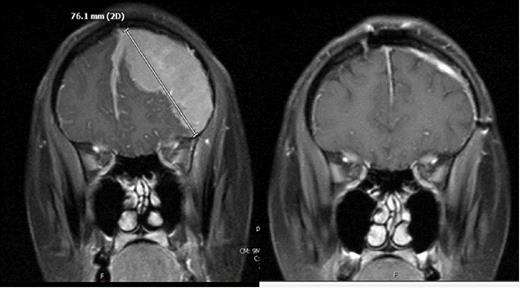

A 38-year-old African American female patient presented with chronic intermittent headaches. MRI of the brain showed a dural-based homogeneously enhancing extra-axial mass along the left hemisphere with extension to the anterior interhemispheric falx and anterior right frontal lobe measuring up to 11 cm. This was found to have a significant mass effect and 1-2 cm left-to-right midline shift on the underlying brain parenchyma with vasogenic edema. The patient underwent an emergent craniotomy and debulking of the mass. The tumor was contained within the anterior and parietal dural matter. The malignant cells stained diffusely positive for CD19, CD20, and CD22 but negative for CD5, CD10, Cyclin D1, and CD56. Ki67 was 10-20%, consistent with extranodal marginal zone lymphoma. Given the location and pathology, the patient was diagnosed with PDL. She was started on treatment with bendamustine and rituximab. She completed six cycles, and post-therapy MRI brain showed complete remission. She continues to do well two years after finishing treatment.